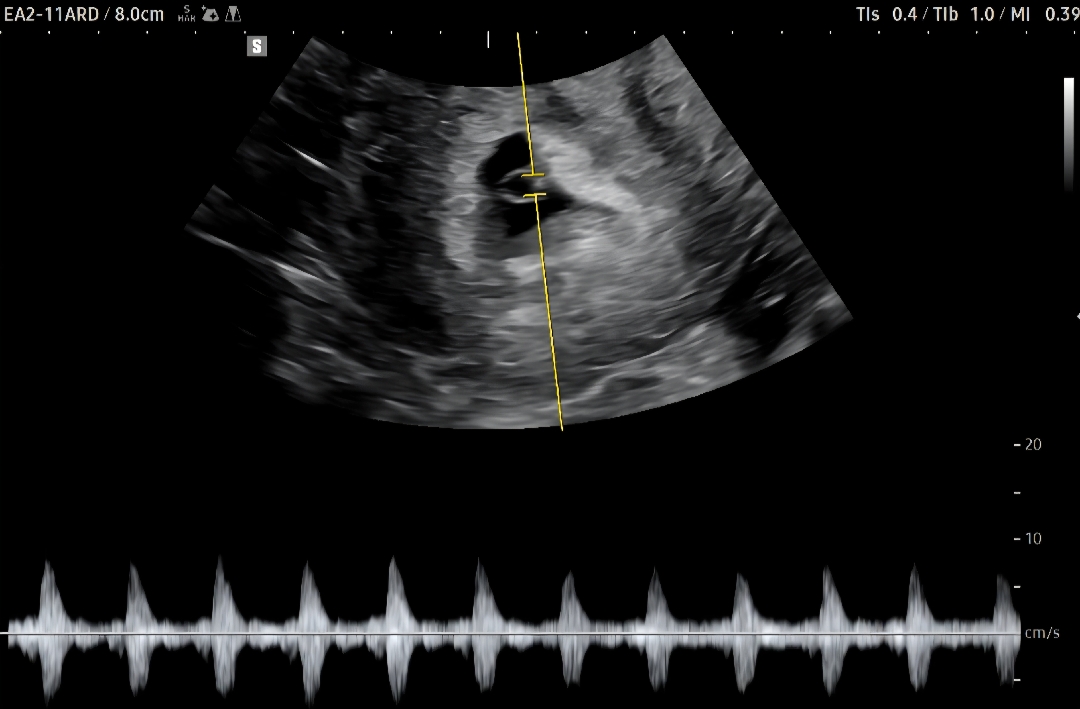

5월 22일 막생이에요! 7월 3일 6주 차로 알고 갔더니 5주 차라 아기집만 봤어요🥲 (배란이 늦었을 수 있다고 하셨어요) 어제 드뎌 난황과 반짝반짝✨ 빛나던 심장 보고 듣고 왔습니다🙊🙊🙊 사실 1차 초음파 때보다 출산 예정일이 더 늦어져서 '잘 자라는 게 맞겠지?'라는 걱정이 되네요🥲 출산예정일이 계속 바꾸신 분 있으실까요?🙏🏻 그래도 심장소리 듣고 왔으니 긍정적으로 이너피스🍀 가져볼까 합니다~ㅎㅎ